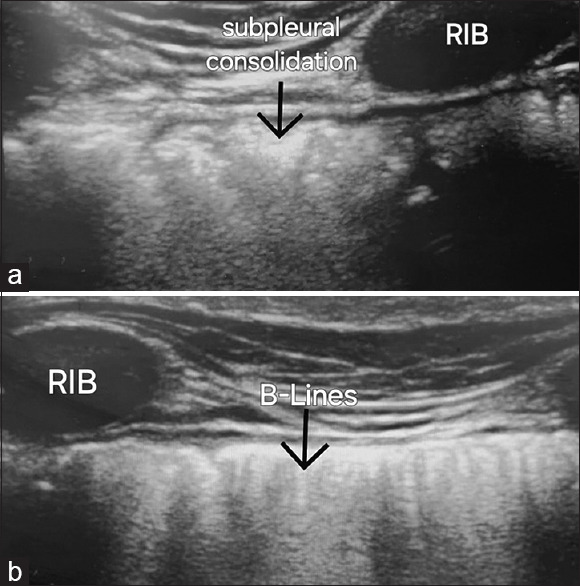

Abstract Image